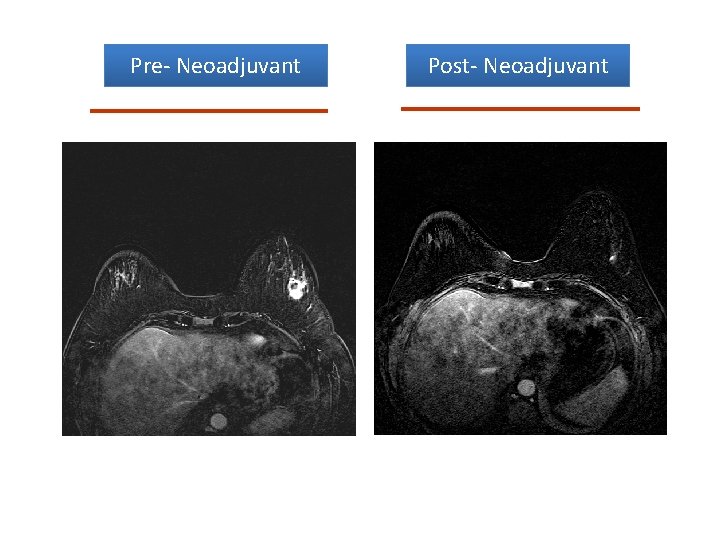

Post- Neoadjuvant Pre- Neoadjuvant p. CR

Pre- Neoadjuvant Post- Neoadjuvant

Loco-Regional Endpoints • In Breast p. CR: – 25 -30% w/ anthracyclines/taxanes – 40 -50% w/ chemo + trastuzamab in HER-2+ – 50 -60% w/ chemo + two anti-HER-2 agents • Axillary p. CR: – 30% w/ anthracyclines – Up to 40% w/ anthracyclines/taxanes – > 50% w/ chemo + anti-HER-2 therapies